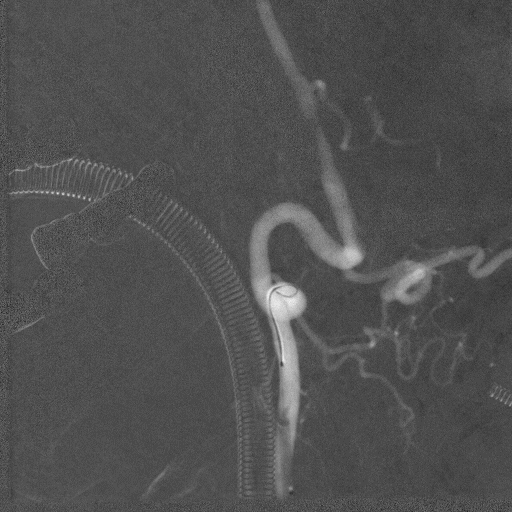

影像信息

主动脉弓上血管多发斑块形成。

左侧锁骨下动脉显示左侧椎动脉开口重度狭窄,狭窄率85%,供血至PICA。

双侧颈动脉造影提示双侧颈内动脉多发斑块形成,远端血管显影良好。

右侧锁骨下动脉造影提示右侧椎动脉主供血,开口无狭窄,椎动脉V4段局限性重度狭窄,狭窄率 80%,远端基底动脉及分支血管显影良好。